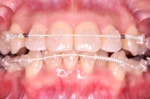

ワイヤーなどを使う矯正装置とは異なり、取り外しができ、装着していても外見上目立たないマウスピースタイプの矯正装置です。

使用時間、使用方法を守らないと治療効果の得られないテクニックになります。

従って、患者様の協力と強い意志が必要になりますので、十分ご理解の上治療をお受けください。

(尚、すべての歯並びに適応されることはありませんので、精密検査及び説明をお受けください。)

ワイヤータイプ 前歯の部分だけ透明で マウスピースタイプ

目立ちにくい type